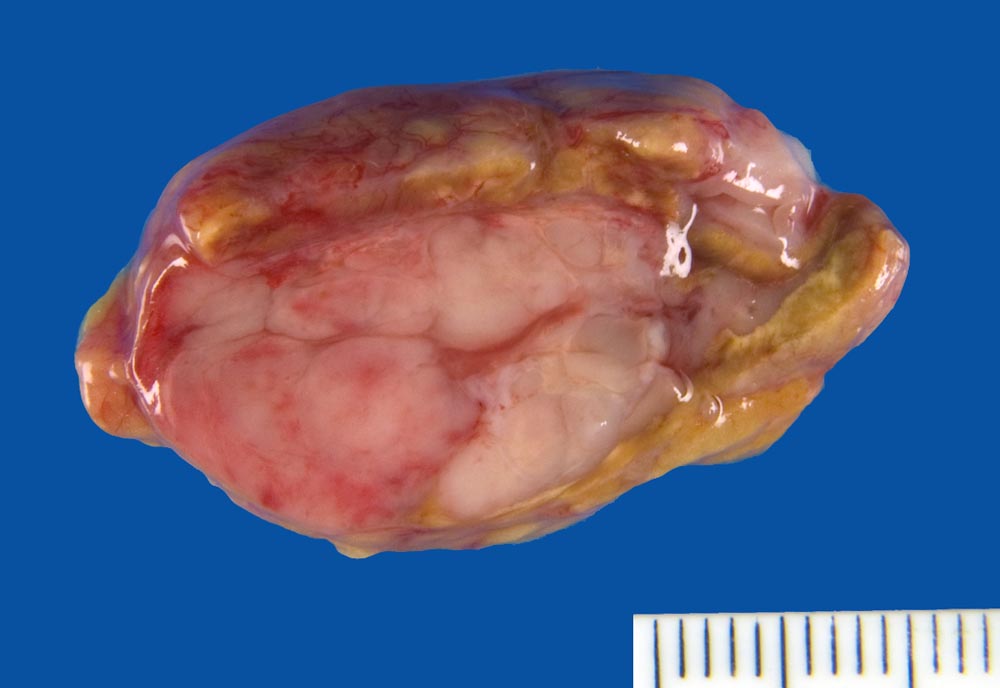

Makroskopisch sind die runden Osteolyseherde gefüllt mit einer weichen gelatinösen fischfleischartigen grauroten Tumormasse. Gelegentlich findet sich anstelle von Osteolysen eine diffuse Osteoporose. In der Knochenmarkbiopsie sind die Plasmazellen vermehrt. Im Gegensatz zu den kleinen Aggregaten von 5 bis 6 Plasmazellen rund um Markarteriolen bei reaktiver Plasmozytose bilden Plasmazellmyelome grössere Herde, Knoten oder flächenhafte Infiltrate. Für ein Plasmazellmyelom spricht eine tumorale Masse von Plasmazellen, welche das ortsständige Knochenmark verdrängt. Wenn über 10% des Markvolumens von klonalen Plasmazellen eingenommen wird, ist die Diagnose eines Plasmazellmyeloms sicher. Je nach klinischer Präsentation liegt dann eine symptomatische oder asymptomatische Verlaufsform vor. Die neoplastischen Zellen produzieren meist monotypische zytoplasmatische Ig (meist IgG, gelegentlich IgA, selten IgD, IgE oder IgM). 85% produzieren Schwerketten und Leichtketten, die restlichen 15% ausschliesslich kappa oder lambda Leichtketten (> 1097). Die klonalen Paraproteine können in den meisten Fällen mit einer Serumelektrophorese oder Urinelektrophorese gemessen werden können.